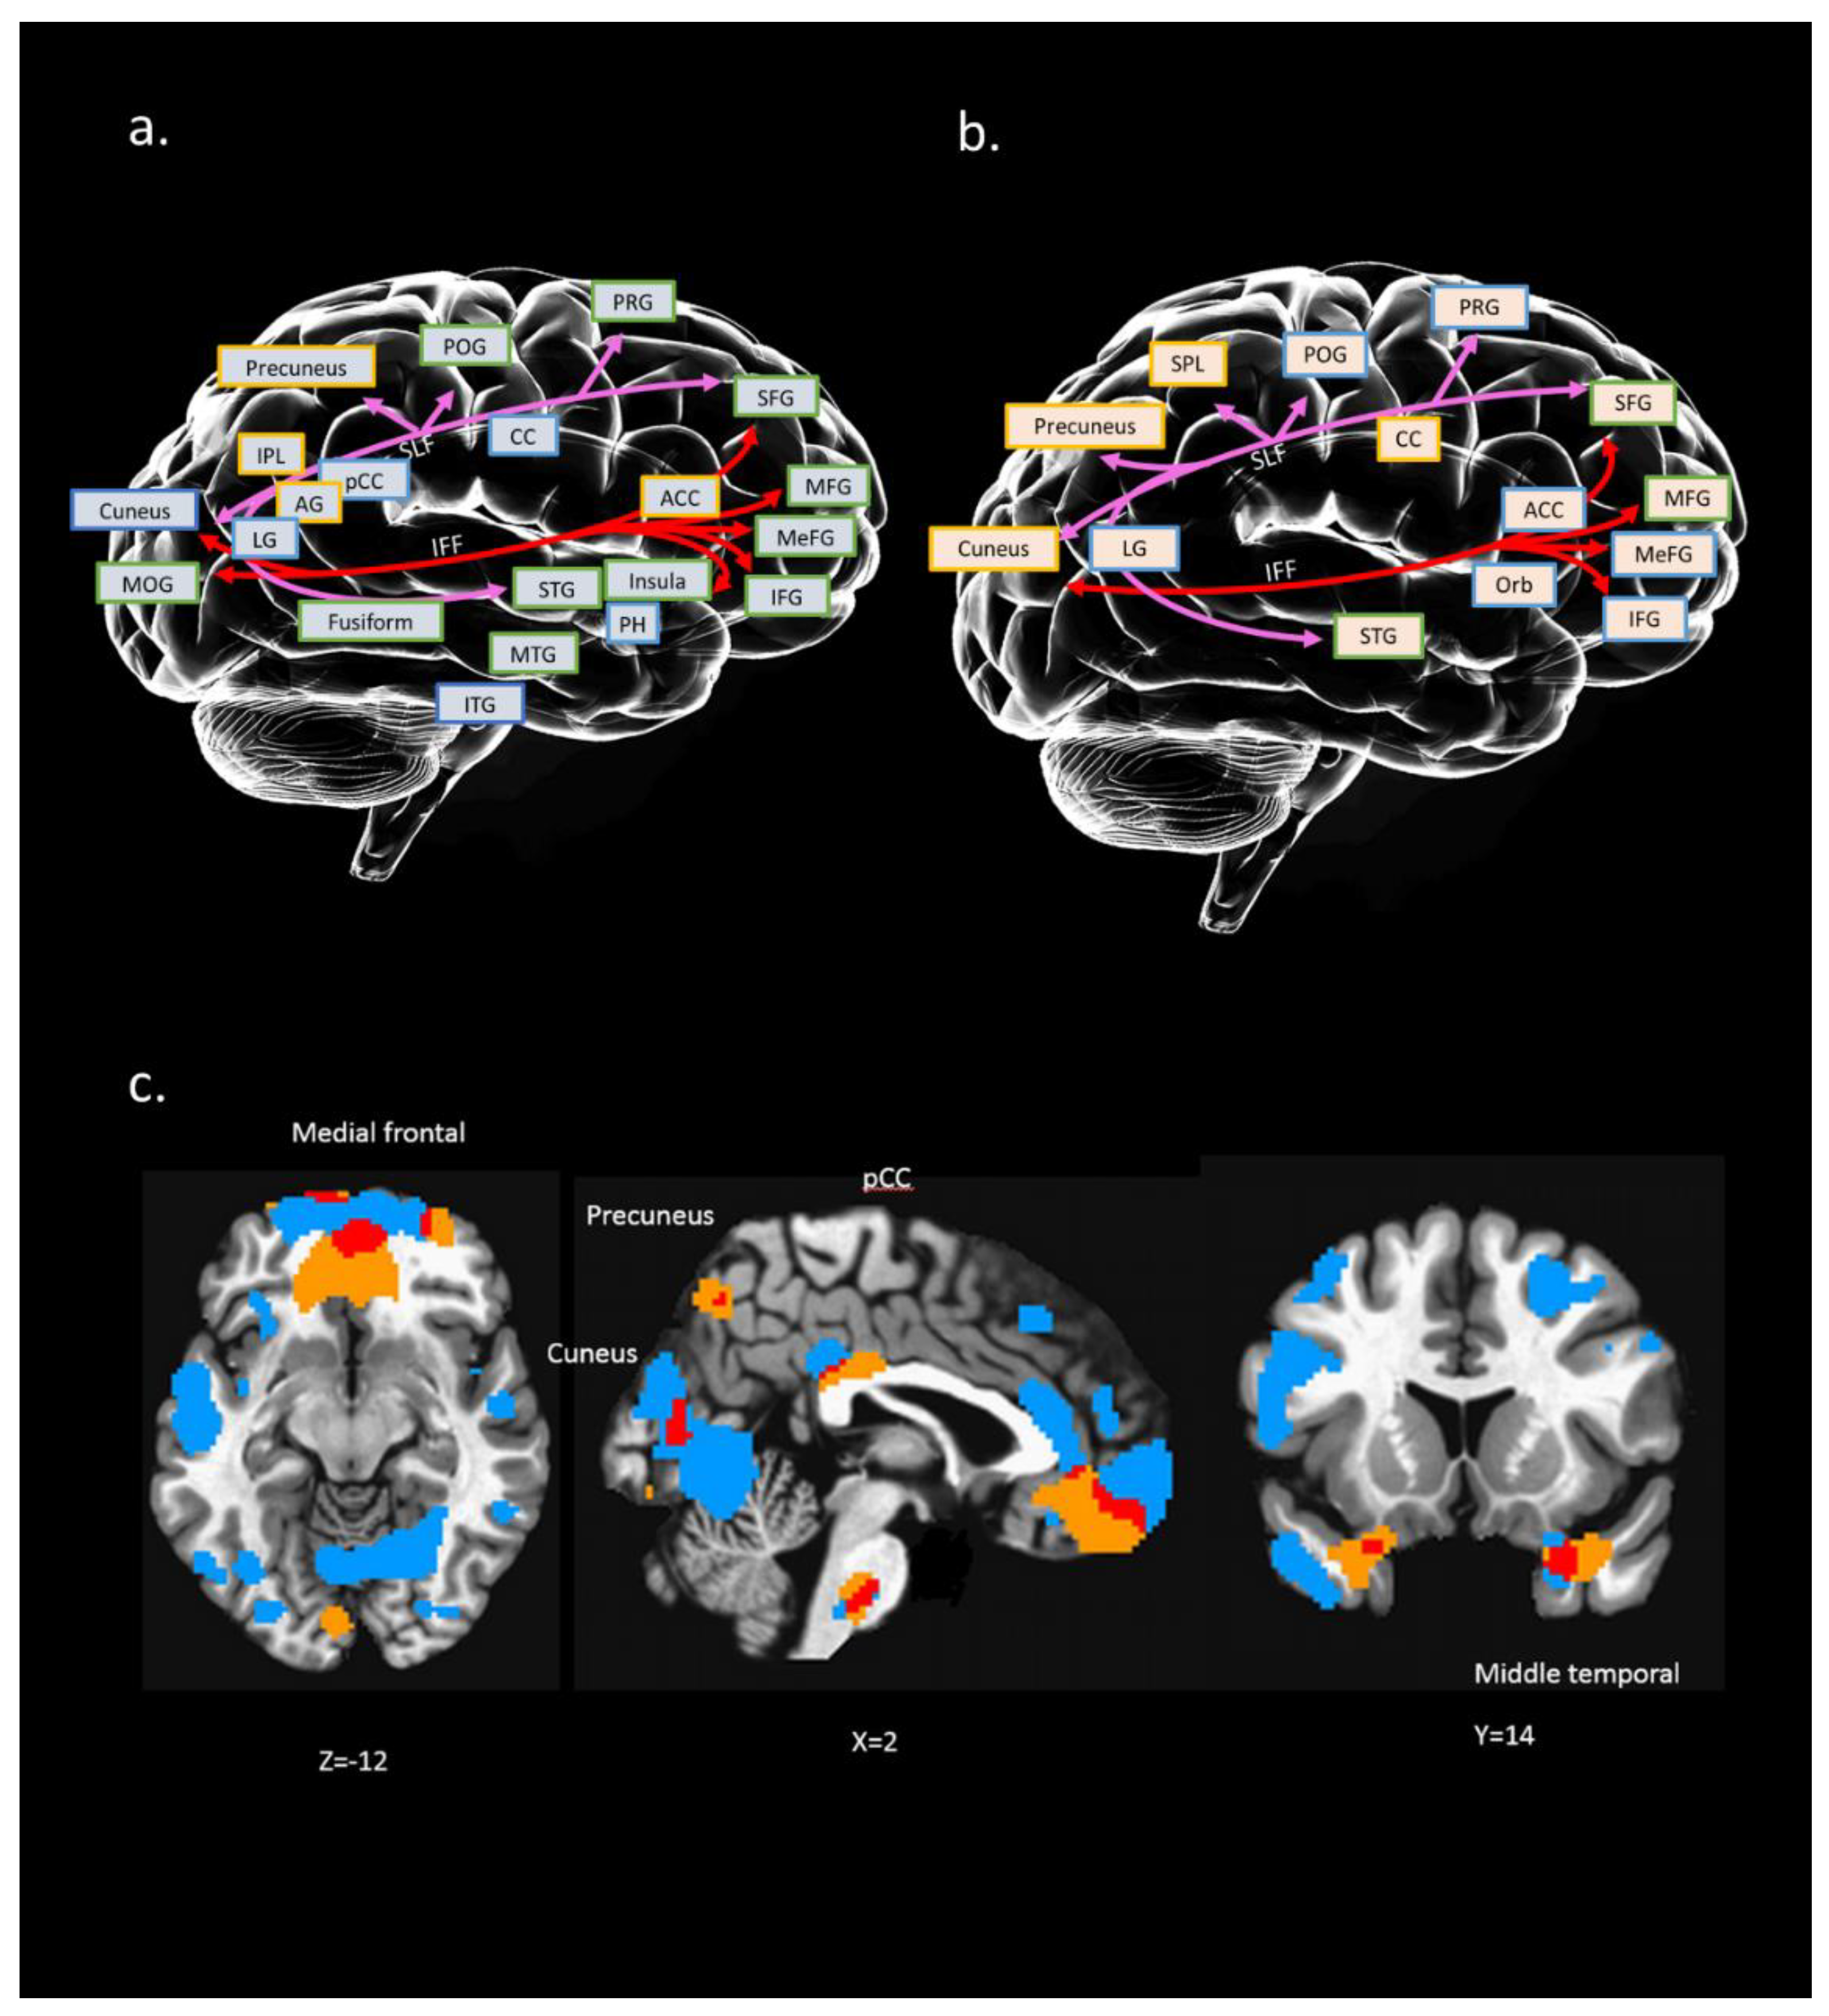

Figure 1.

The results of IC #23 in relation to the RSA (Resilience Scale for Adults) subscale of personal strength (RSA_p). The spatial maps shown in this figure were transformed into Z values visualized at |Z| > 2.5. ICs = independent components.

Figure 1 displays IC#23′s spatial maps of GMV (e.g., VBM), ALFF, and RD tensor-based WM tracts. For GMV map, the negative contributing regions (i.e., significantly negative correlations) were mainly in the temporal lobe (superior, middle, and inferior temporal gyrus), and secondly in lingual gyrus, precentral, superior frontal gyrus, middle frontal gyrus, inferior frontal gyrus, medial frontal gyrus, postcentral gyrus, middle occipital gyrus, insula, parahippocampal gyrus and the cuneus. Whereas the positive contributing regions included precentral gyrus, postcentral gyrus, frontal lobe (superior, middle, inferior, and medial), insula, inferior parietal lobule, superior temporal gyrus, precuneus, anterior cingulate, middle occipital gyrus, fusiform and angular gyrus. For the ALFF map, the negative contributing regions are mainly in the medial frontal gyrus, precentral gyrus and superior temporal lobe, and were in the minority in the anterior cingulate, orbital gyrus, superior frontal gyrus, middle frontal gyrus and postcentral gyrus, inferior frontal gyrus, and lingual gyrus. Whereas the positive contributing regions are mainly in the superior frontal gyrus, middle frontal gyrus, precuneus, cuneus, cingulate gyrus, superior temporal gyrus, and superior parietal lobule. For WM tracts map, the negative contributing clusters are mainly in the SLF and IFF.

Figure 2 further summarizes the main results of spatial maps across different neuroimaging modalities (i.e., rfMRI, sMRI, and dMRI). The purpose of this approach is to measure the interaction of the results with (a) known WM tracts for dMRI and (b) known brain regions for rfMRI and sMRI. Furthermore, we only present the significant results of ALFF and GM regions that are near to the WM tracts.

Figure 2.

Conceptual illustration to present possible relation between brain regions (structural and functional) and connection paths [white matter (WM) tracts]: (a) interaction between WM tracts and GM region of IC#23; (b) interaction between WM tracts and ALFF regions of IC#23. A colored square with a yellow edge indicates positive clusters in this region. A colored square with a blue edge indicates negative clusters in this region. Colored square with green edge indicates both positive and negative clusters in this region; (c) overlapping (marked in red) between IC #23’s GM (marked in blue) and ALFF regions (marked in yellow); x, y, z = 2, 14, −12. Distinct WM tracts were marked with different colors. PRG: precentral gyrus; POG: postcentral gyrus; MFG: middle frontal gyrus; MeFG: medial frontal gyrus; IFG: inferior frontal gyrus; CC: cingulate cortex; ACC: anterior cingulate; pCC: posterior cingulate cortex; PH: parahippocampal gyrus; STG: superior temporal gyrus; MTG: middle temporal gyrus; ITG: inferior temporal gyrus; IPL: inferior parietal gyrus; LG: lingual gyrus; MOG: middle occipital gyrus; Orb: orbital gyrus; AG: angular gyrus.

We found that the neural substrates of IC#23 cover a wide range of brain structures and functions, including the frontal region (e.g., medial frontal, superior frontal), temporal region (e.g., superior temporal, middle temporal, inferior temporal), parietal region (e.g., superior parietal, inferior parietal), occipital region (e.g., middle occipital, cuneus, precuneus), and even the subcortical region (e.g., cingulate gyrus, parahippocampal gyrus) (see Figure 2). Also, two tracts in IC#23 were SLF and IFF, which connected the frontal, occipital, parietal, and temporal lobes.